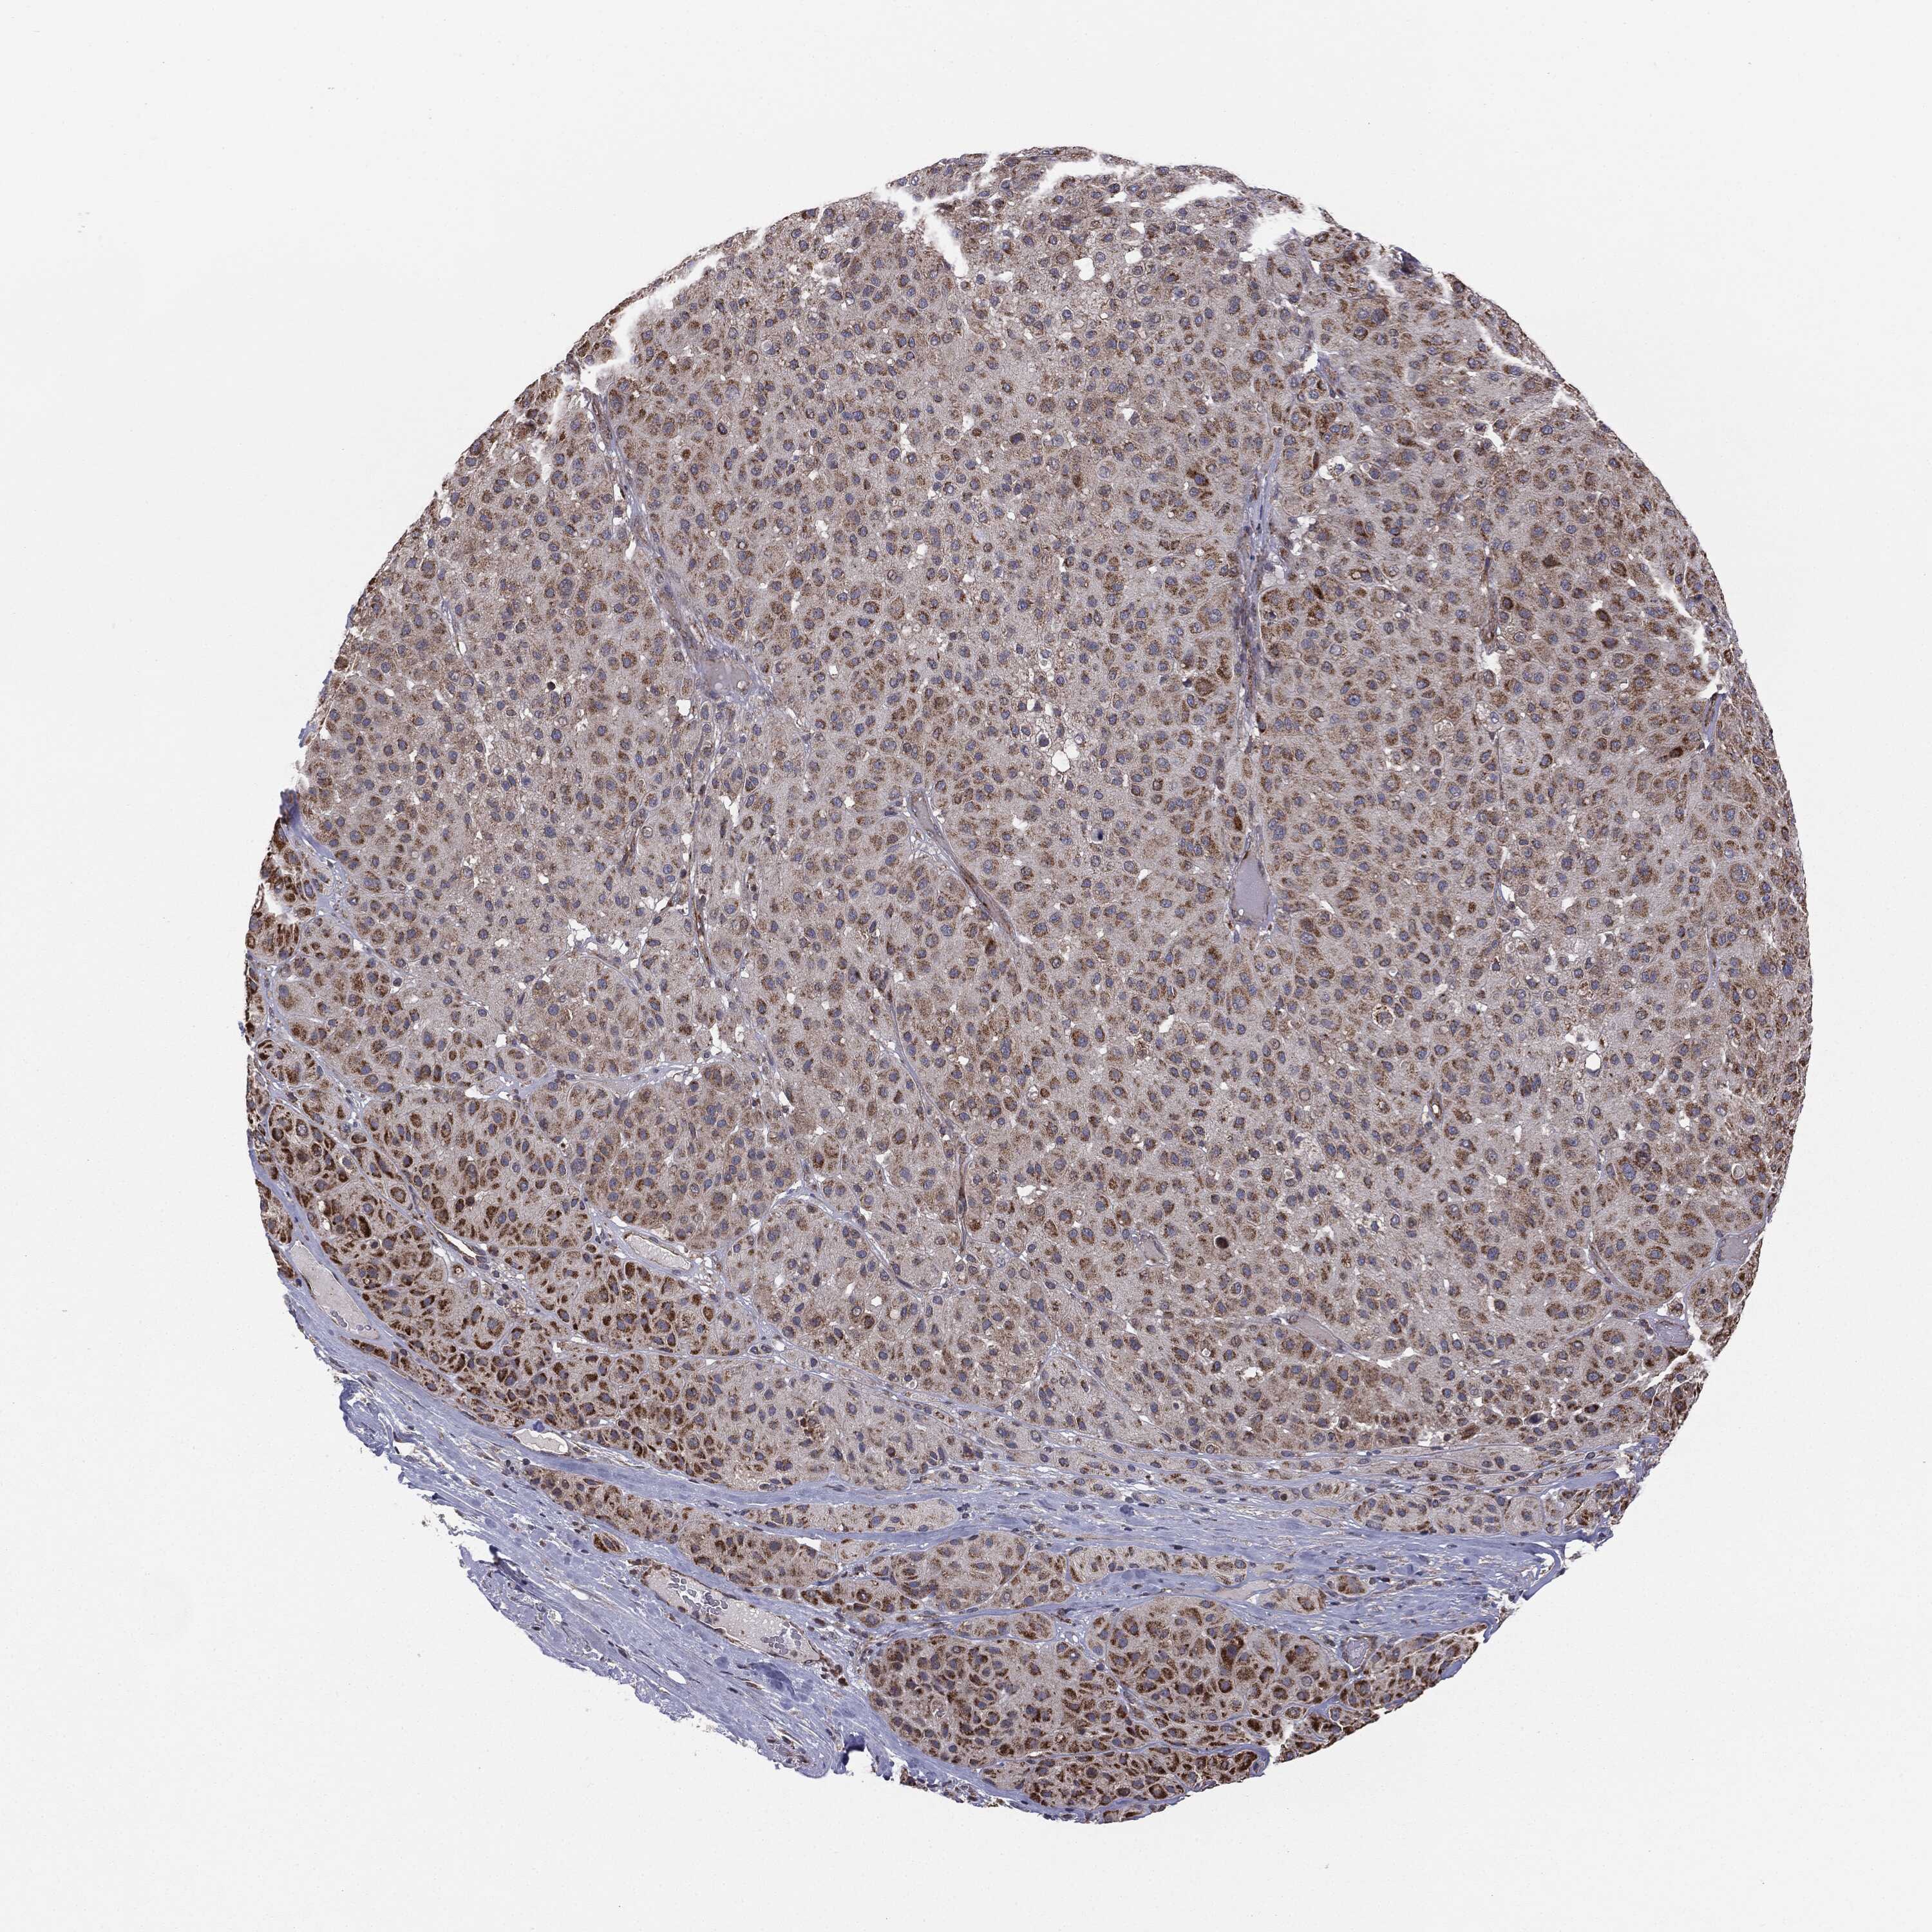

MELANOMA - Protein expressioni

A mouse-over function shows sample information and annotation data. Click on an image to view it in a full screen mode. Samples can be filtered based on level of antibody staining by selecting one or several of the following categories: high, medium, low and not detected. The assay and annotation is described here.

Note that samples used for immunohistochemistry by the Human Protein Atlas do not correspond to samples in the TCGA dataset.

Antibody stainingi

Antibody staining in the annotated cell types in the current human tissue is reported as not detected, low, medium, or high, based on conventional immunohistochemistry profiling in selected tissues. This score is based on the combination of the staining intensity and fraction of stained cells.

Each image is clickable and will lead to virtual microscopy that enables deeper exploration of all samples and also displays staining intensity scores, fraction scores and subcellular localization as well as patient and tissue information for each sample.

CAB069425

CAB080053

CAB080065

CAB080070

CAB080081

CAB080095

CAB080097

Staining

High

Medium

Low

Not detected

Intensity

Strong

Moderate

Weak

Negative

Quantity

>75%

75%-25%

<25%

None

Location

Nuclear

Cytoplasmic/membranous

Cytoplasmic/membranous,nuclear

Malignant melanoma, NOS

Malignant melanoma, Metastatic site